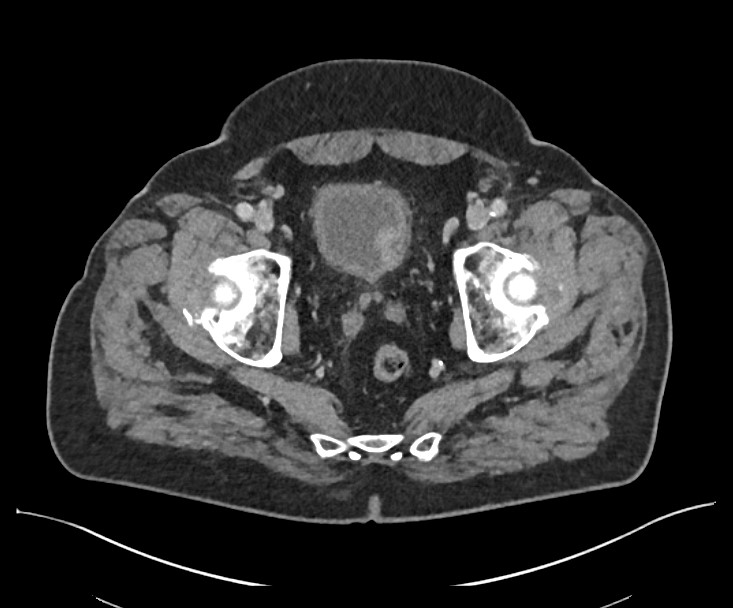

L'examen clinique révèle état fébrile à 38.7°C, une sensibilité abdominale diffuse avec une légère défense en fosse iliaque droite et un signe de McBurney positif. L’épididyme droit est également douloureux. Le bilan biologique montre une hyperleucocytose à 15 G/L et une CRP à 8,6 mg/L. L'examen d'urine objective une leucocyturie importante avec bactériurie. Une ultrasonographie bedside de la vessie met en évidence une masse intravésicale exophytique de 2 cm sur la paroi latérale confirmée par un scanner abdominal (cf. image).

Le diagnostic retenu est une infection urinaire compliquée, associée à une tumeur vésicale découverte fortuitement. Le bilan réalisé par la suite révèle un carcinome urothélial non invasif de bas grade.